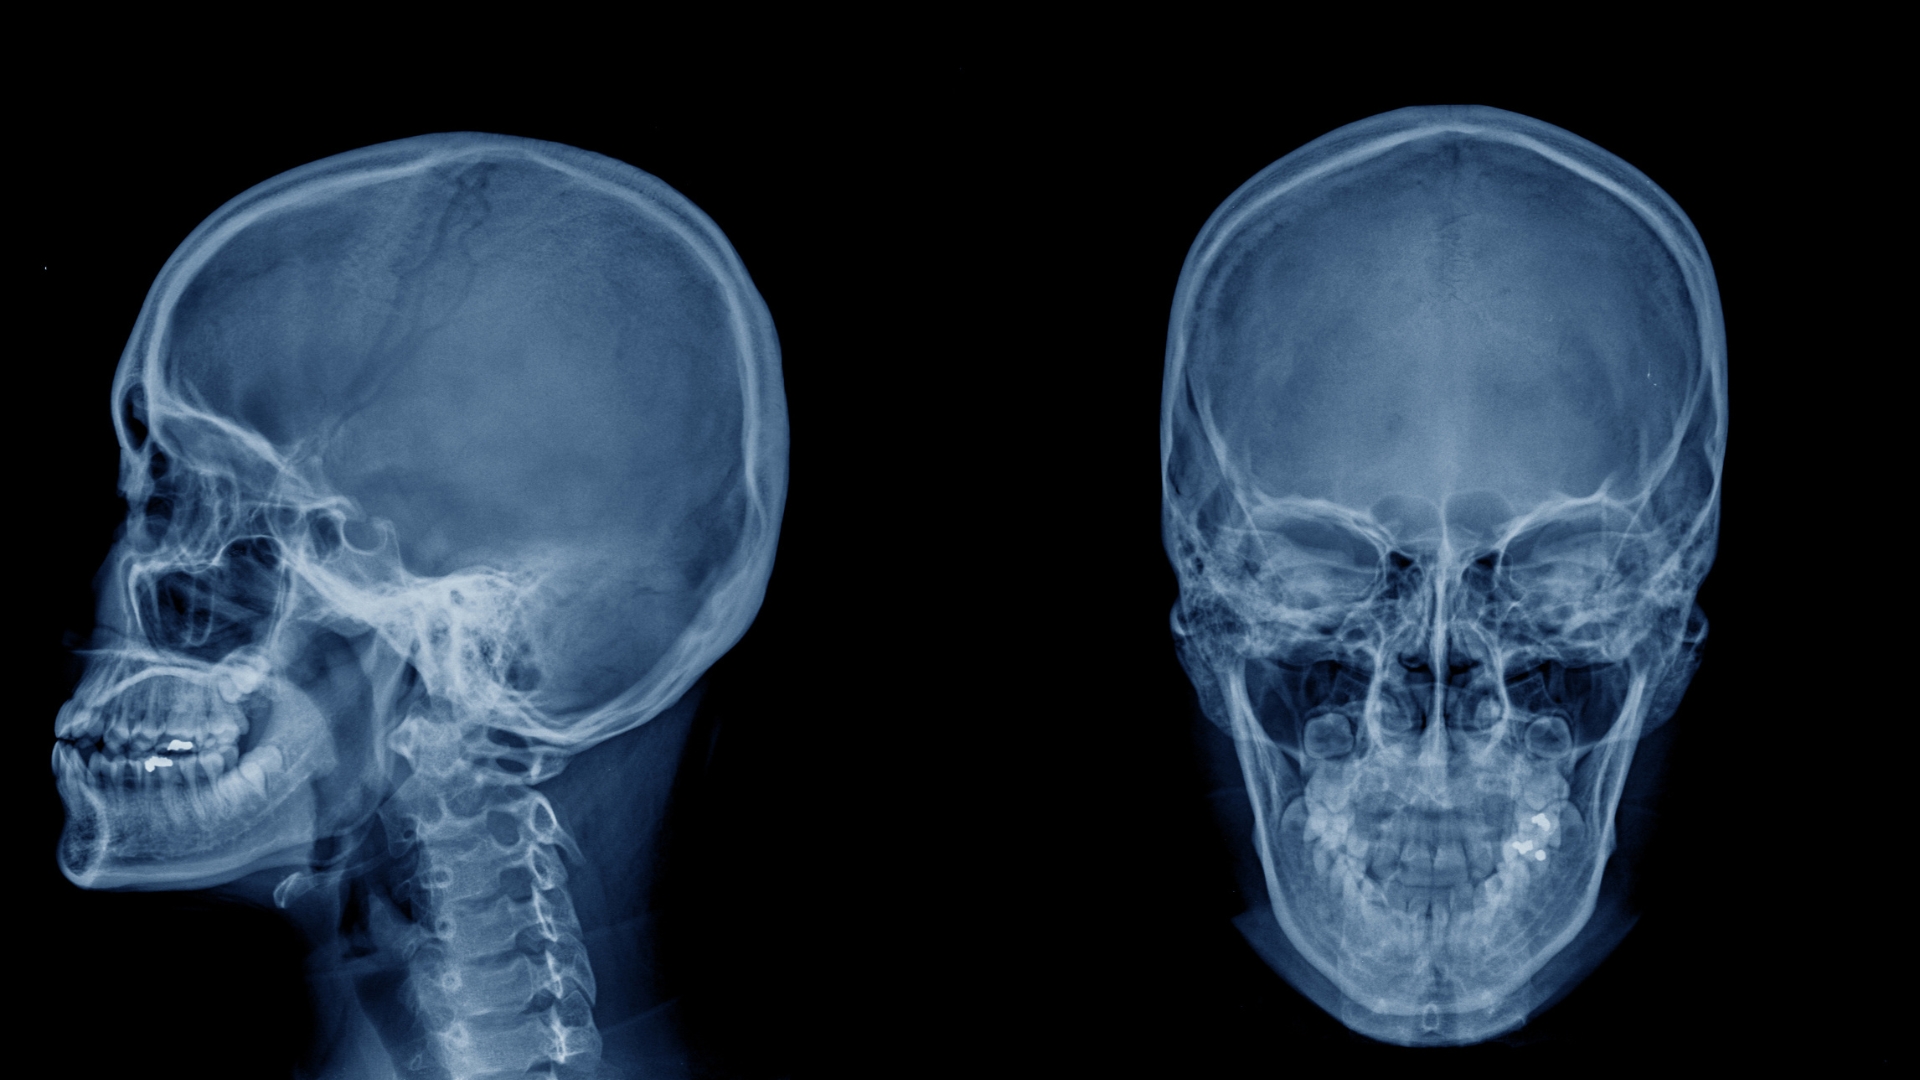

Chụp X-quang não là phương pháp chẩn đoán hình ảnh sử dụng tia X để ghi lại hình ảnh cấu trúc xương sọ. Hình ảnh có thể hiển thị trên phim truyền thống hoặc hệ thống kỹ thuật số, giúp bác sĩ đánh giá mật độ và hình dạng của xương.

Kỹ thuật này đặc biệt hữu ích trong việc phát hiện các tổn thương như nứt xương, gãy xương, gãy lún hoặc biến dạng hộp sọ sau va chạm mạnh. Nhờ hình ảnh thu được, bác sĩ có thể xác định vị trí tổn thương, mức độ ảnh hưởng và đưa ra hướng xử trí phù hợp.

Phương pháp chủ yếu khảo sát các thành phần xương, bao gồm vòm sọ, nền sọ và các đường khớp giữa các mảnh xương. Khi xảy ra chấn thương đầu, phim chụp có thể cho thấy đường gãy mảnh hoặc tổn thương lan rộng ở nhiều vị trí khác nhau. Đây là cơ sở quan trọng để đánh giá nguy cơ biến chứng và quyết định có cần thực hiện thêm các kỹ thuật hình ảnh chuyên sâu hay không.

Thông thường, chụp X-quang sọ não được thực hiện ở ít nhất hai tư thế để tăng độ chính xác:

Tư thế thẳng: Giúp quan sát tổng thể cấu trúc phía trước và phía sau của hộp sọ.

Tư thế nghiêng: Hỗ trợ phát hiện các đường gãy ở vùng thái dương, đỉnh đầu hoặc phía bên của sọ.

Việc kết hợp nhiều góc chụp giúp hạn chế bỏ sót các vết nứt nhỏ và nâng cao khả năng phát hiện tổn thương xương trong giai đoạn đầu.